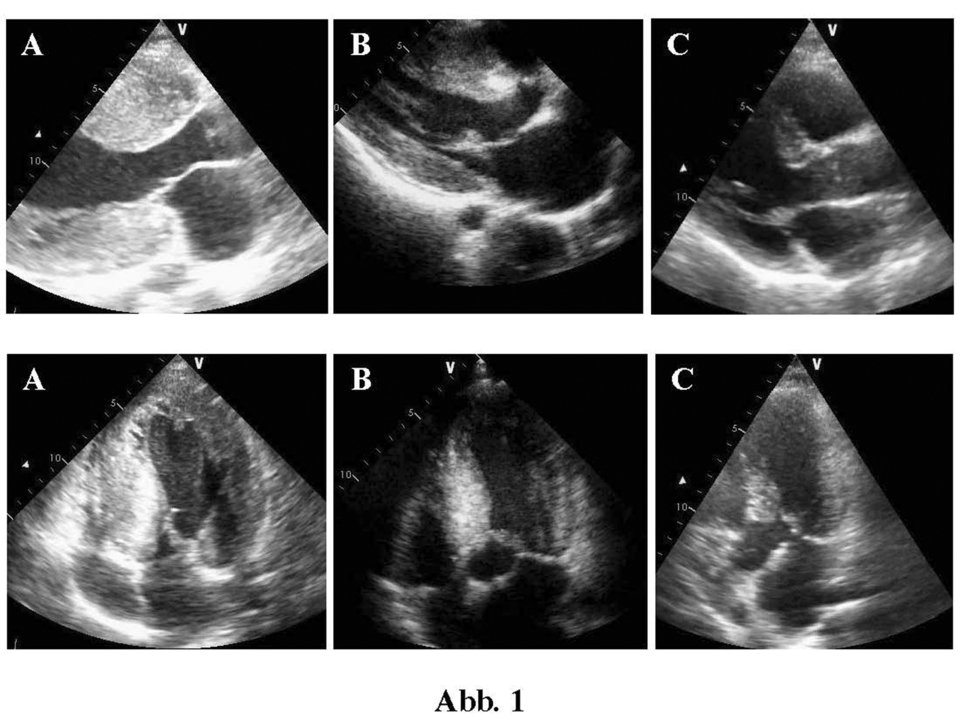

Die Echokardiographie von drei Geschwistern mit HOCM zeigt die deutliche Variabilität der Hypertrophie in Diastole. Die Echokardiographie von drei Geschwistern mit HOCM zeigt die deutliche Variabilität der Hypertrophie in Diastole. © Quelle Text und Abb.: Koljaja-Batzner et al. internistische praxis 2018; 59: 187-201, © Mediengruppe Oberfranken - Fachverlage GmbH & Co. KG, Kulmbach

Die Echokardiographie von drei Geschwistern mit HOCM zeigt die deutliche Variabilität der Hypertrophie in Diastole (oben) und Systole (unten). Die Echokardiographie von drei Geschwistern mit HOCM zeigt die deutliche Variabilität der Hypertrophie in Diastole (oben) und Systole (unten). © Quelle Text und Abb.: Koljaja-Batzner et al. internistische praxis 2018; 59: 187-201, © Mediengruppe Oberfranken - Fachverlage GmbH & Co. KG, Kulmbach